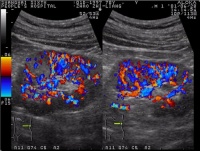

3.超声扫描:超声检查是最简便无创伤的检查方法,可作为常规体检的一部分,肾脏内超过lcm肿块即可被超声扫描,所发现重要的是鉴别肿块是否是肾癌,肾癌为实性肿块由于其内部可能有出血坏死囊性变,因此回声不均匀,一般为低回声。肾癌的境界不甚清晰这一点和肾囊肿不同,肾内占位性病变都可能引起肾盂肾盏肾窦脂肪变形或断裂肾乳头状囊腺癌,超声检查酷似囊肿并可能有钙化,肾癌和囊肿难以鉴别时可以穿刺,在超声引导下穿刺是比较安全的,穿刺液可作细胞学检查并行囊肿造影,囊肿液常为清澈无肿瘤细胞低脂肪造影时囊壁光滑可肯定为良性病变,如穿刺液为血性应想到肿瘤可能,在抽出液中找到肿瘤细胞造影时囊壁不光滑,即可诊断为恶性肿瘤。肾血管平滑肌脂肪瘤为肾内实性肿瘤,其超声表现为脂肪组织的强回声,容易和肾癌相鉴别。在超声检查发现肾癌时亦应注意肿瘤是否穿透包膜,肾周脂肪组织有无肿大淋巴结,肾静脉下腔静脉内有无癌栓,肝脏有无转移等。